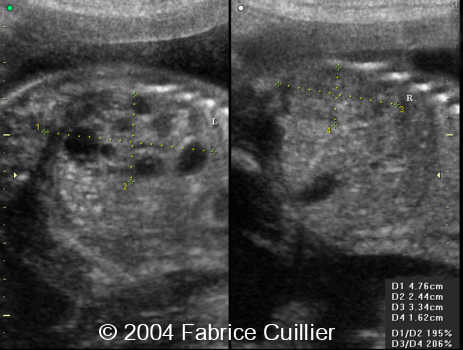

Multicystic kidney disease, unilateral, in a twin

This is a case of unilateral multicystic kidney disease in a twin with no other anomalies.